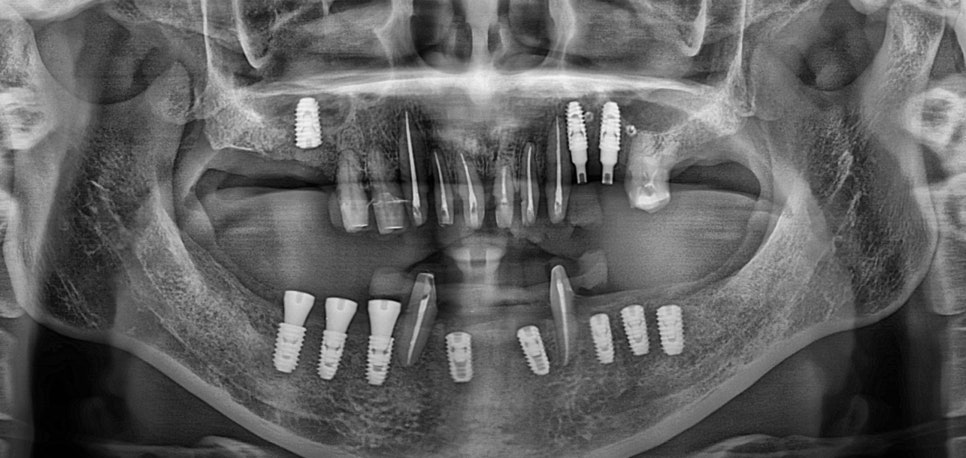

표시된 치아 부분들에는 뼈이식을 진행 후 임플란트를 식립 하였습니다.

잇몸뼈가 없는 상태에서 임플란트를 식립하게 되면

뿌리역할을 하는 픽스쳐 (제일 밑 지대주) 가 제대로 고정이 안되서 제대로된 임플란트 식립이 불가합니다.

위의 사진은 충분한 뼈이식 진행 후 픽스쳐를 식립하였고 나머지 치아들은 크라운 씌우기 전 신경치료 진행한 모습 입니다.

수술은 나눠서 진행 하였고 뼈가 제대로 차오를때까지 2~3개월 소요 후 최종 보철 까지 마무리 하였습니다.